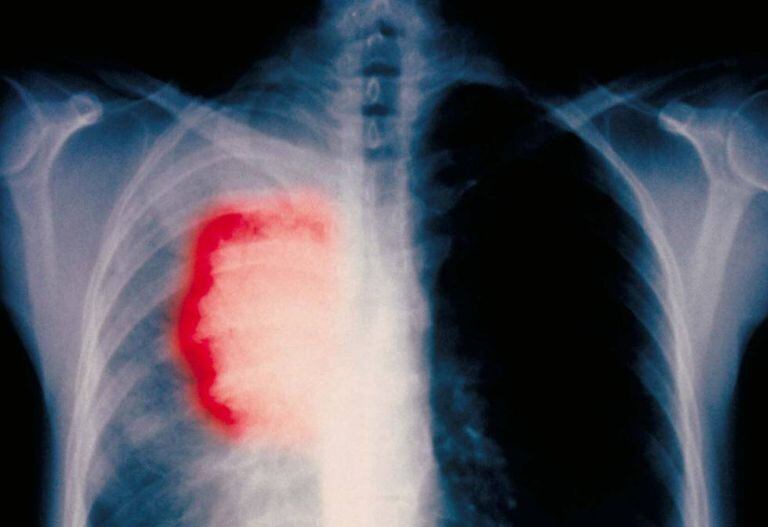

“O câncer de pulmão é o que mais mata no mundo todo, e a razão é que quase sempre o diagnosticamos tarde”, diz em seu consultório o pneumologista Avi Spira, diretor do Centro Oncológico da Universidade de Boston (EUA). “Quando os pacientes têm os primeiros sintomas e vêm ao médico, geralmente o tumor se espalhou para fora do pulmão e não há nada que possamos fazer”, lamenta.

Esse tipo de câncer mata mais de 1,5 milhão de pessoas por ano no mundo, e a Organização Mundial da Saúde prevê que sua incidência aumentará 70% nas próximas duas décadas. Esta guerra afeta desproporcionalmente os países em desenvolvimento, e para vencê-la é crucial obter um bom método de diagnóstico precoce.